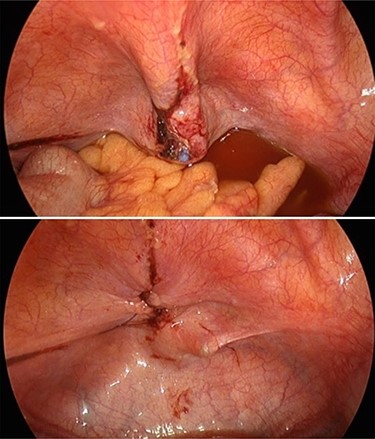

The patient then underwent a laparoscopy, which confirmed a bladder dome perforation with the tip of the Foley’s catheter. Her pelvic organs appeared normal. Incidentally, violin-like liver adhesions were found during her laparoscopy in keeping with Fitz-Hugh–Curtis syndrome (FHCS). The bladder dome was repaired laparoscopically, and peritoneal fluid was sent for microscopy and culture. Retrospective re-evaluation of CT images confirmed the diagnosis (Figs 2 and 3).

Intraoperative photo showing tip of Foley catheter protruding through bladder wall and subsequent repair.